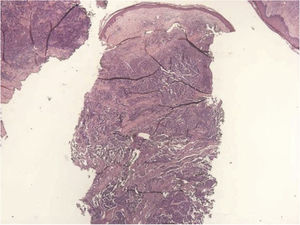

Homem branco de 67 anos procurou o ambulatório de dermatologia com antecedente pessoal de hipertensão arterial sistêmica, diabetes mellitus tipo 2 e dislipidemia, em uso de insulina, losartana, hidroclorotiazida, atenolol, ácido acetilsalicílico, rosuvastatina e fibrato, após seis meses de evolução de nódulo eritêmato‐violáceo (fig. 1), assintomático, de crescimento rápido, que media 3cm2, na perna direita, sem linfadenomegalias palpáveis. A biópsia incisional (figs. 2 e 3) da lesão revelou, na histopatologia, tumor dérmico com arranjo trabecular, composto por pequenas células azuis com citoplasma escasso e núcleo compacto. A imuno‐histoquímica foi positiva para cromogranina e citoqueratina 20, firmando diagnóstico de CCM. No retorno ambulatorial, solicitamos tomografia computadorizada de tórax, abdômen e pelve, que não evidenciou comprometimento de órgãos internos ou linfadenomegalias. Os testes para imunossupressão e as sorologias eram todos negativos. Em seguida, o paciente foi enviado para cirurgia oncológica, que fez pesquisa de linfonodo sentinela, sem evidência de comprometimento neoplásico. Foi feita exérese ampla, medindo 7,7 × 6,8 × 0,8cm, e a histopatologia demonstrou CCM com margens de resseção livres de comprometimento.